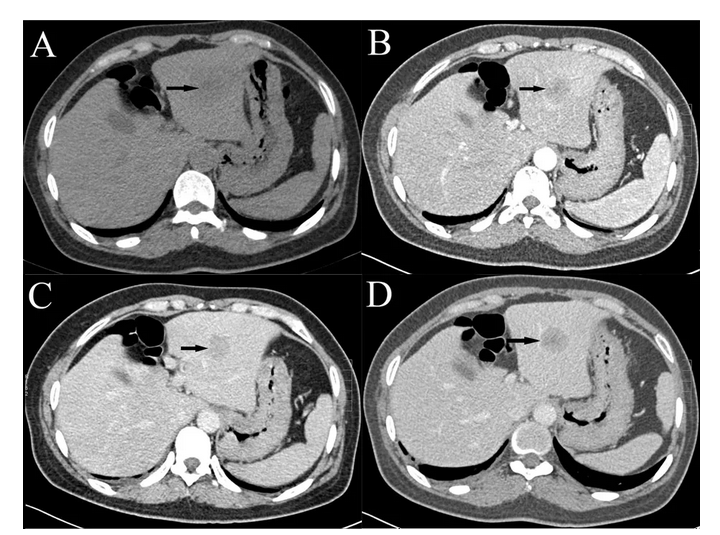

原发性肝细胞癌的ct和mri诊断

原发性肝细胞癌行三次debtace治疗一例